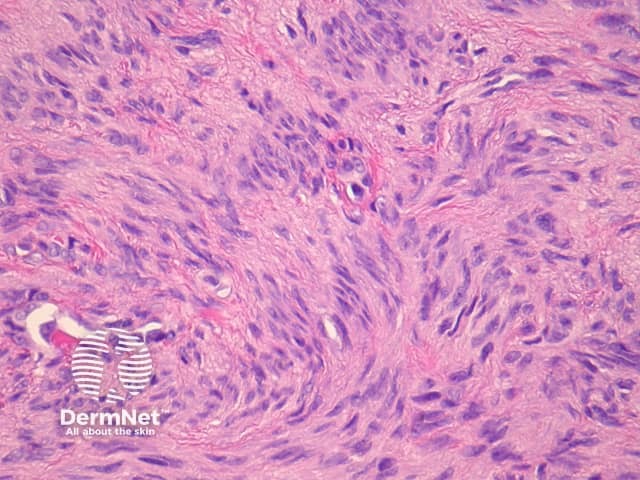

Sections through epithelioid dermatofibroma show a centrally located, circumscribed tumour underlying an epidermal collarette. The tumour is composed of cells arranged in sheets and sometimes a storiform pattern. Individual cells show epithelioid morphology with abundant eosinophilic cytoplasm with round vesicular nuclei and prominent nucleoli (figures 5, 6). The cells may be markedly enlarged and display some nuclear atypia and mitoses. There is frequently an associated inflammatory cell infiltrate which can be helpful for the diagnosis.

Figure 5

Figure 6